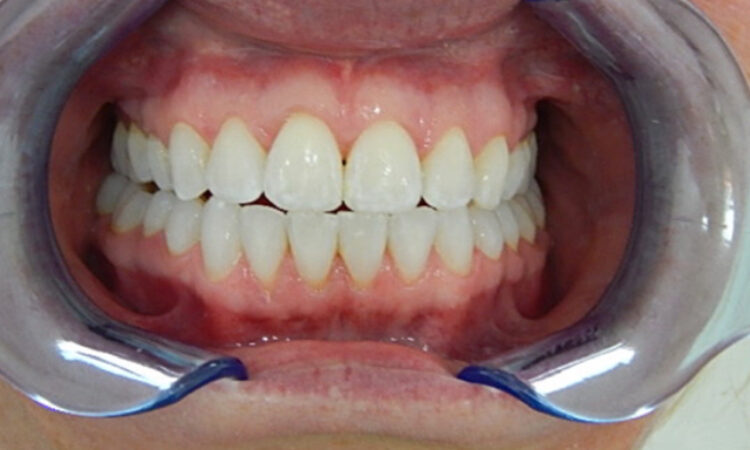

Before - puredental After - puredental

Case 17 - Invisalign®